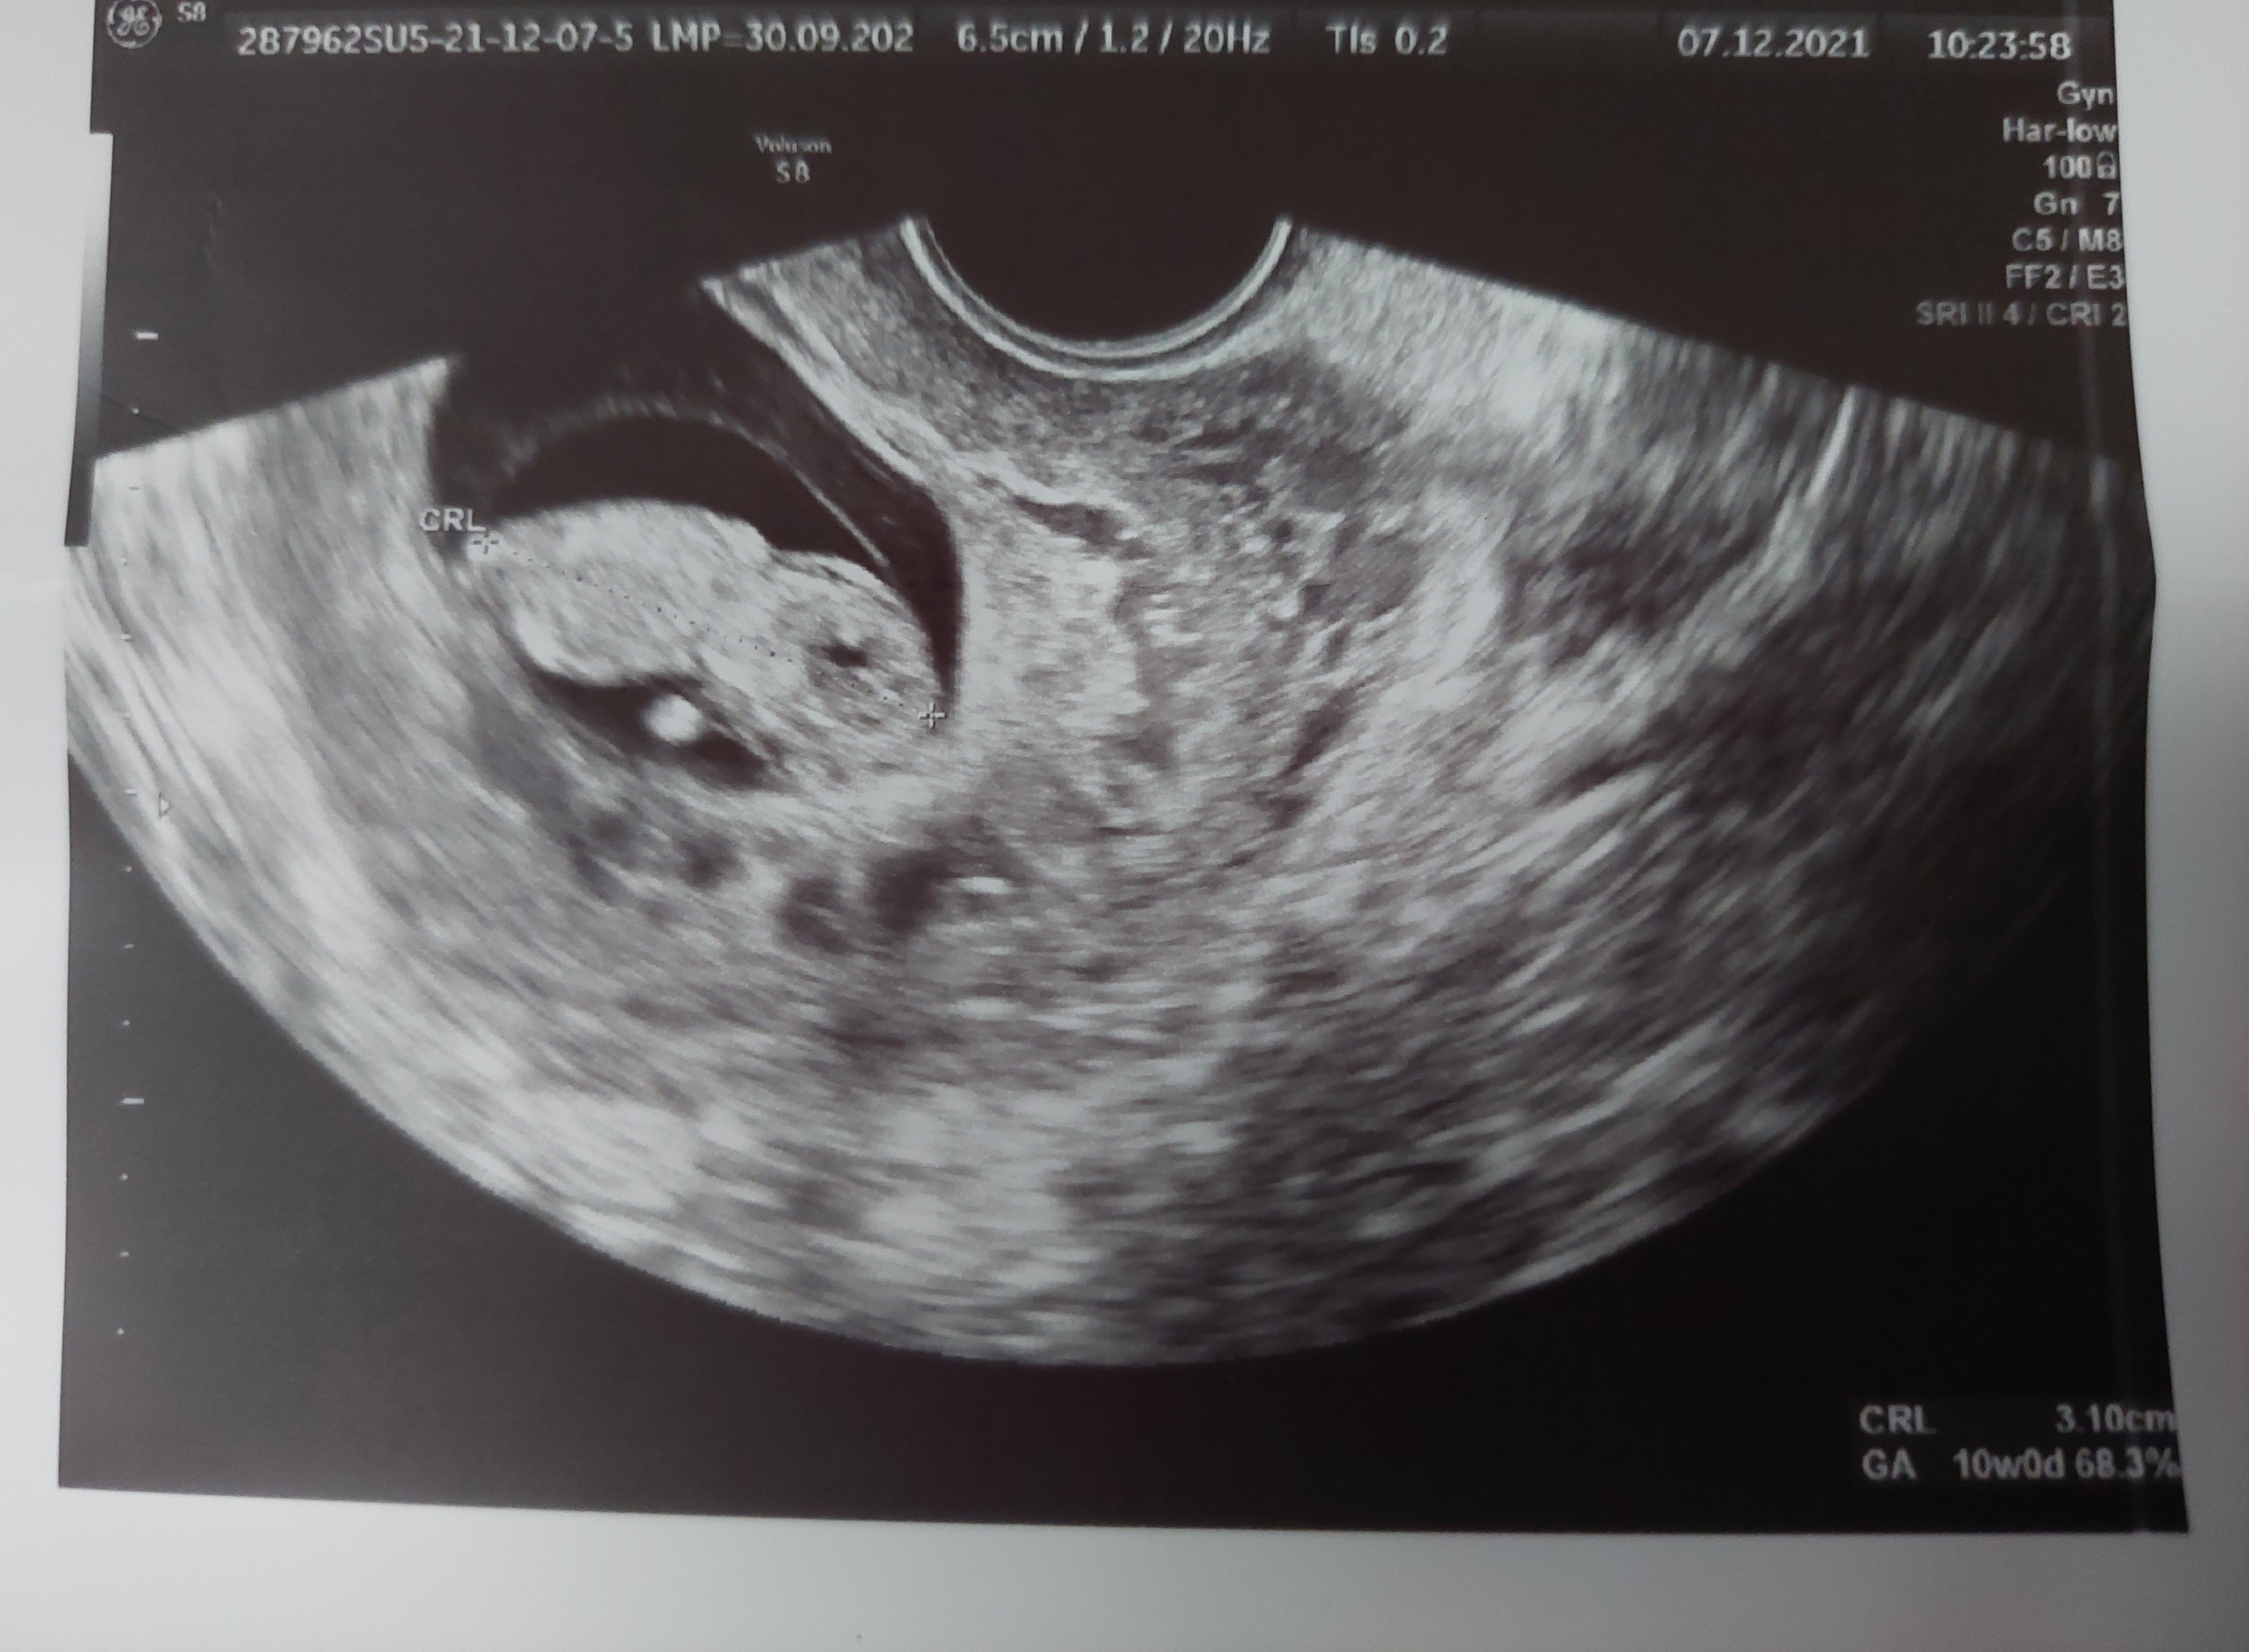

Dziewczyny przebrnęłam wreszcie przez dzisiejsze posty i mogę Wam zdać relację z mojej dzisiejszej wizyty. Otóż mój okruszek to jak to powiedziała Pani doktor to już "malutki człowieczek" 😁 Wszystko wygląda dobrze.

Dziś 9t4d a maluszek ma CRL 3,10 cm (10t0d). Serduszko biło, ale nie wiem jakie było FHR. Najważjiejsze że +. Kolejna wizyta 21.12. Bardzo się cieszę, że tuż przed świętami, bo będę spokojniejsza. 27.12 mam prenatalne plus PAPPa więc super.

Załączniki

• 20211207_113428.jpg

20211207_113428.jpg

2,4 MB · Wyświetleń: 102